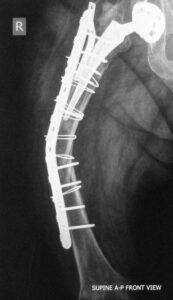

- Περιπροθετικό κάταγμα. Κάταγμα του οστού σε γειτνίαση με ορθοπεδικό εμφύτευμα. Διακρίνεται το κάταγμα κάτωθεν του εμφυτεύματος.

- Περιπροθετικό κάταγμα ανάμεσα σε δύο εμφυτεύματα με αστοχία της πλάκας οστεοσύνθεσης.